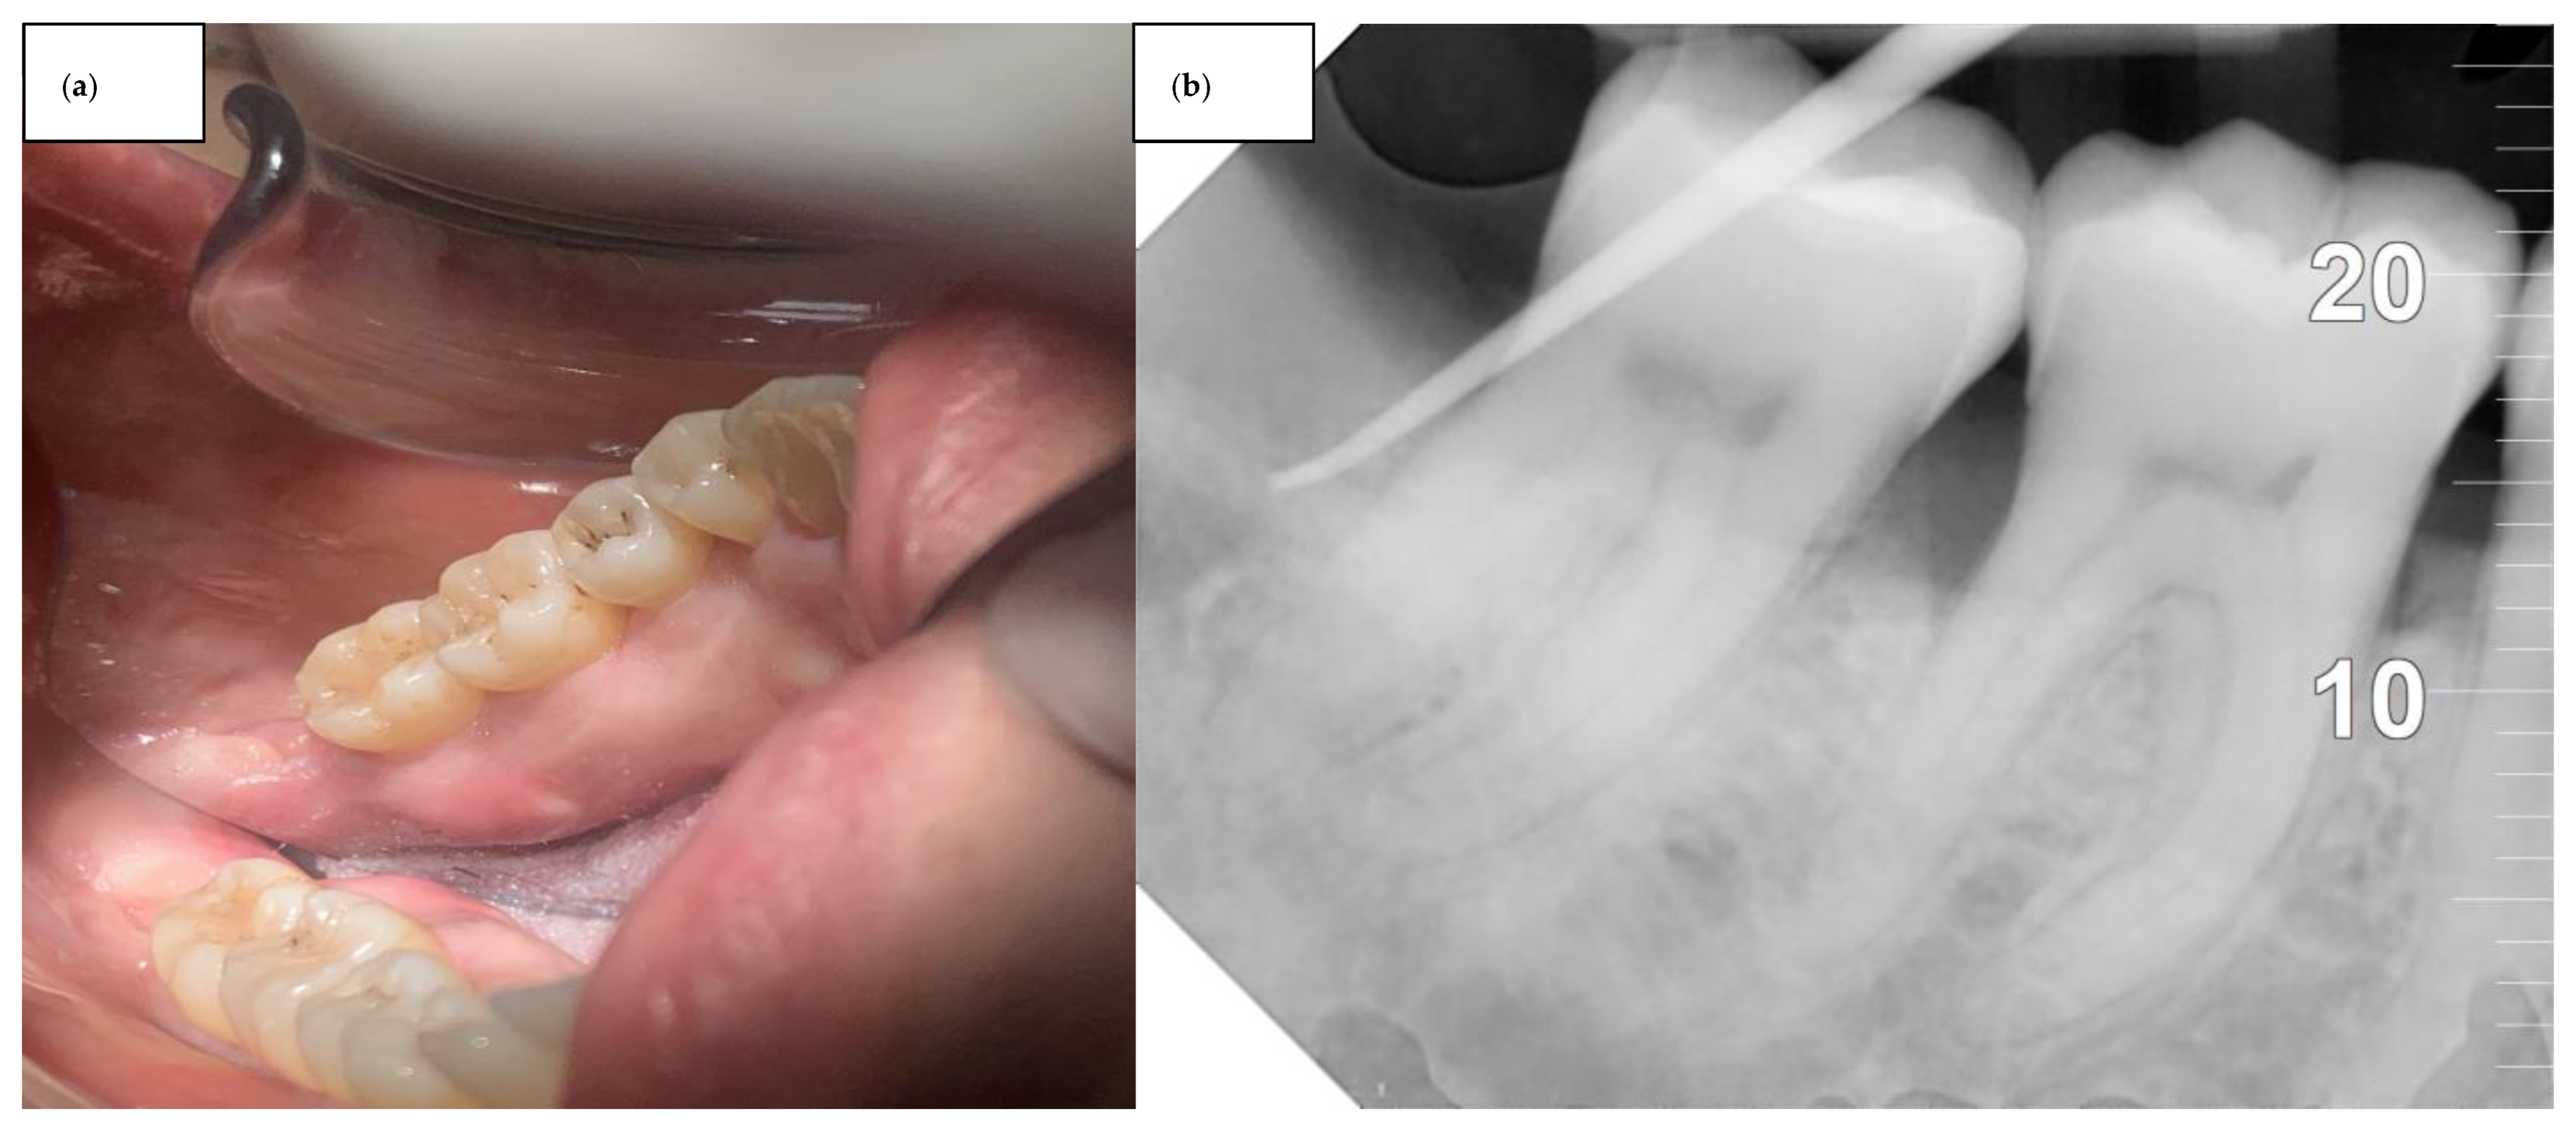

2. Case Series